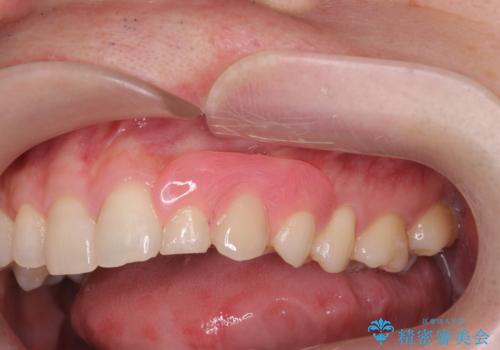

[骨の隆起で話しづらい]舌のスペースを確保する骨隆起切除術

- 虫歯の治療を希望され来院されました。

治療が進む中で舌のスペースが狭く、息苦しさや話しづらいことに悩まれていることの改善として骨隆起の切除を行いました。

切除術は静脈内鎮静法を併用し、リラックスした状態で行いました。

骨隆起は歯ぎしりや食いしばりと言った、歯や顎骨に大きな力がかかる場合に生じる場合があります。

通常義歯を作製する場合に、邪魔となり切除することがありますが今回は舌のスペースが狭く話しづらいとのことで切除術を施行しました。